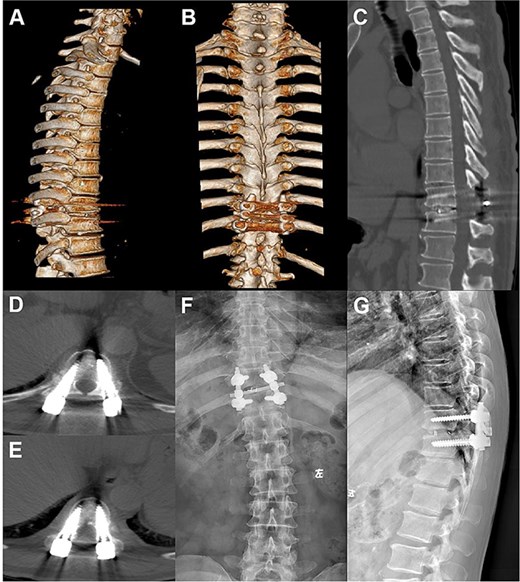

A 66-year-old male presented with a 1-year history of progressive low back pain and bilateral lower limb numbness, intensifying over the preceding month. Symptoms began insidiously without trauma and progressively worsened with prolonged standing and walking, improving with rest. The patient described deep, aching pain that significantly impacted his daily activities. Physical examination revealed bilateral lower limb numbness, especially prominent in the anterior thighs, an unsteady gait with a broad-based stance, decreased quadriceps muscle strength, reduced sensation below the navel extending to the groin, and positive bilateral Babinski signs indicating upper motor neuron involvement. Initial external X-rays suggested only L4 vertebral displacement, inconsistent with the clinical findings, prompting hospital admission for further evaluation. Refined imaging studies revealed previously unrecognized pathology. X-ray (Fig. 1A) and CT (Fig. 1B–D) demonstrated concomitant T10 vertebral body slippage, while MRI (Fig. 1E) showed severe T10/11 spinal cord compression with associated signal changes. The patient was diagnosed with thoracic spinal stenosis due to T10–T11 vertebral slip, explaining the bilateral lower extremity neurological symptoms and gait instability. Given the prolonged symptom duration, recurrent nature, and functional impact, surgical intervention was indicated after multidisciplinary discussion. The patient underwent T10–T11 thoracic interbody fusion with comprehensive decompression under general anesthesia. The procedure included herniated disc material removal, extensive posterior decompression, precise pedicle screw and titanium rod placement for stabilization, and autologous iliac crest bone grafting for interbody fusion. Postoperative management included comprehensive pain control and neurological monitoring. Follow-up X-ray (Fig. 2A and B) and CT (Fig. 2C–E) demonstrated successful vertebral realignment with the internal fixation in the ideal position. By postoperative Day 6, the patient reported significant back pain and leg numbness relief. Progressive improvement with structured physical therapy led to discharge on Day 10. One-year follow-up examination (Fig. 3) revealed stable fixation with continued symptom resolution, enabling free ambulation and complete return to normal activities.

Postoperative follow-up images. (A–D) Repeat CT plain and 3D reconstruction at 6 months postoperatively showed ideal position of the T10–11 internal fixation and fusion device, straight posterior margin of the vertebral body, and no obvious signs of compression of the dural sac. (E, F) Review X-ray at 1 year postoperatively showed that the internal fixation device was in place without obvious dislocation, and the vertebral body slippage was satisfactorily repositioned.